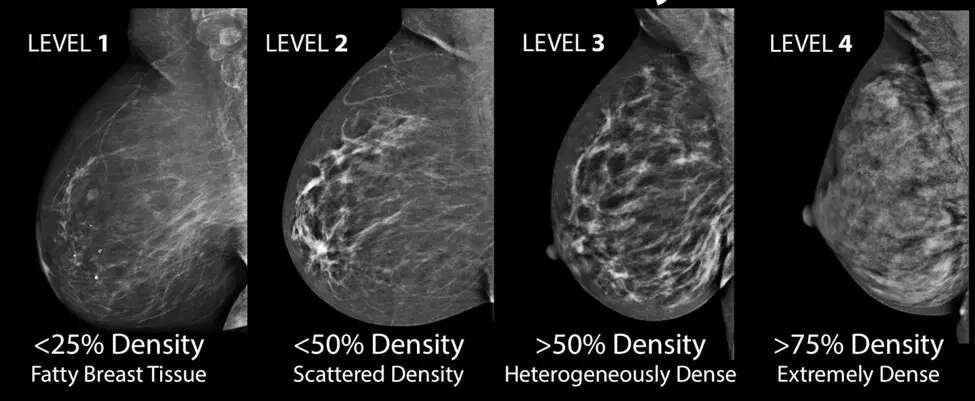

第三是乳腺致密程度。

这一点绝大多数人都不知道。研究发现,致密型乳腺患癌几率更高。这不是摸起来的感觉,而是指医学影像中的特征。通常,脂肪越少,腺体越多的乳房,致密度越高。

从左到右,致密程度逐渐增加。最左边乳腺含大量脂肪,致密度最低,因此影像上很多看似透明的区域;而最右边则几乎全是腺体,致密度非常高。

所以,并不是简单的罩杯大就容易得乳腺癌。如果是脂肪为主,那么风险并不会增加。

为什么致密乳腺发病率更高?目前还不完全清楚,但可能和乳腺癌来源有关。第一期提到过,乳腺癌通常来自乳腺导管和腺泡细胞,而不是脂肪细胞。因此,含腺体多的致密型乳腺,或许有更多可能癌变的细胞。

致密性乳腺还带来另一个麻烦,就是使得X线难以检测出肿瘤,这导致筛查难度增加,容易耽误早期干预机会。